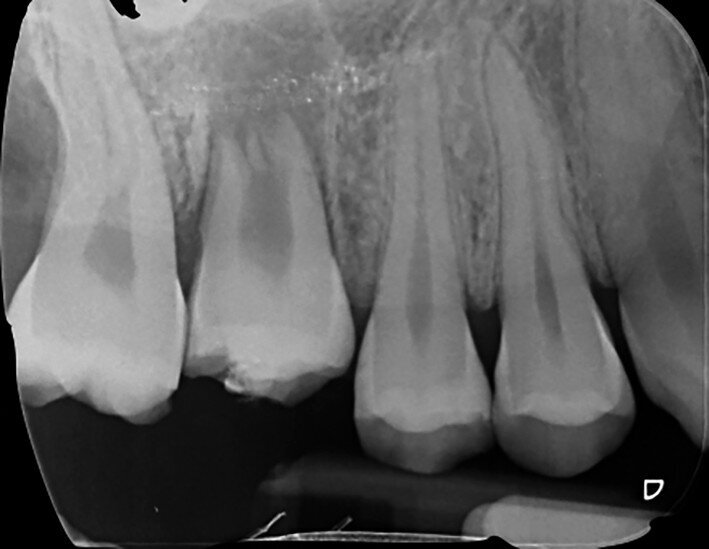

Fig. 3: Pre-op periapical radiograph.

A 47-year-old male patient in a good medical condition and a non-smoker was referred to our dental practice for endodontic retreatment of the right maxillary second molar. The dental history revealed that the tooth had been endodontically treated three months before because of acute pulpitis. After the treatment, the patient complained of pain on chewing. Antibiotics and a non-steroidal anti-inflammatory drug were prescribed, but the pain remained. After a month, a sinus tract appeared. The tooth was retreated in another practice without success. The clinical inspection revealed the presence of a sinus tract near the apical region of tooth #17. The tooth had been prepared for a full crown, but was without even a temporary crown, and the access cavity had been closed with temporary filling material. Cracks were evident on the buccal and mesial surfaces. Periodontal probing showed a deep pocket (> 12 mm) on the distal aspect of the root trunk (Figs. 1 & 2). The periapical radiograph showed a radiolucency between the roots of the second and third molars. The radiographic appearance of the endodontic treatment was good, without clear evidence of periapical radiolucencies (Fig. 3). A perforation of the pulp chamber floor was suspected. A CBCT scan was performed (Figs. 4–7), and it confirmed the suspicion of perforation, along with the presence of a large periradicular radiolucency and an unfavourable root shape.